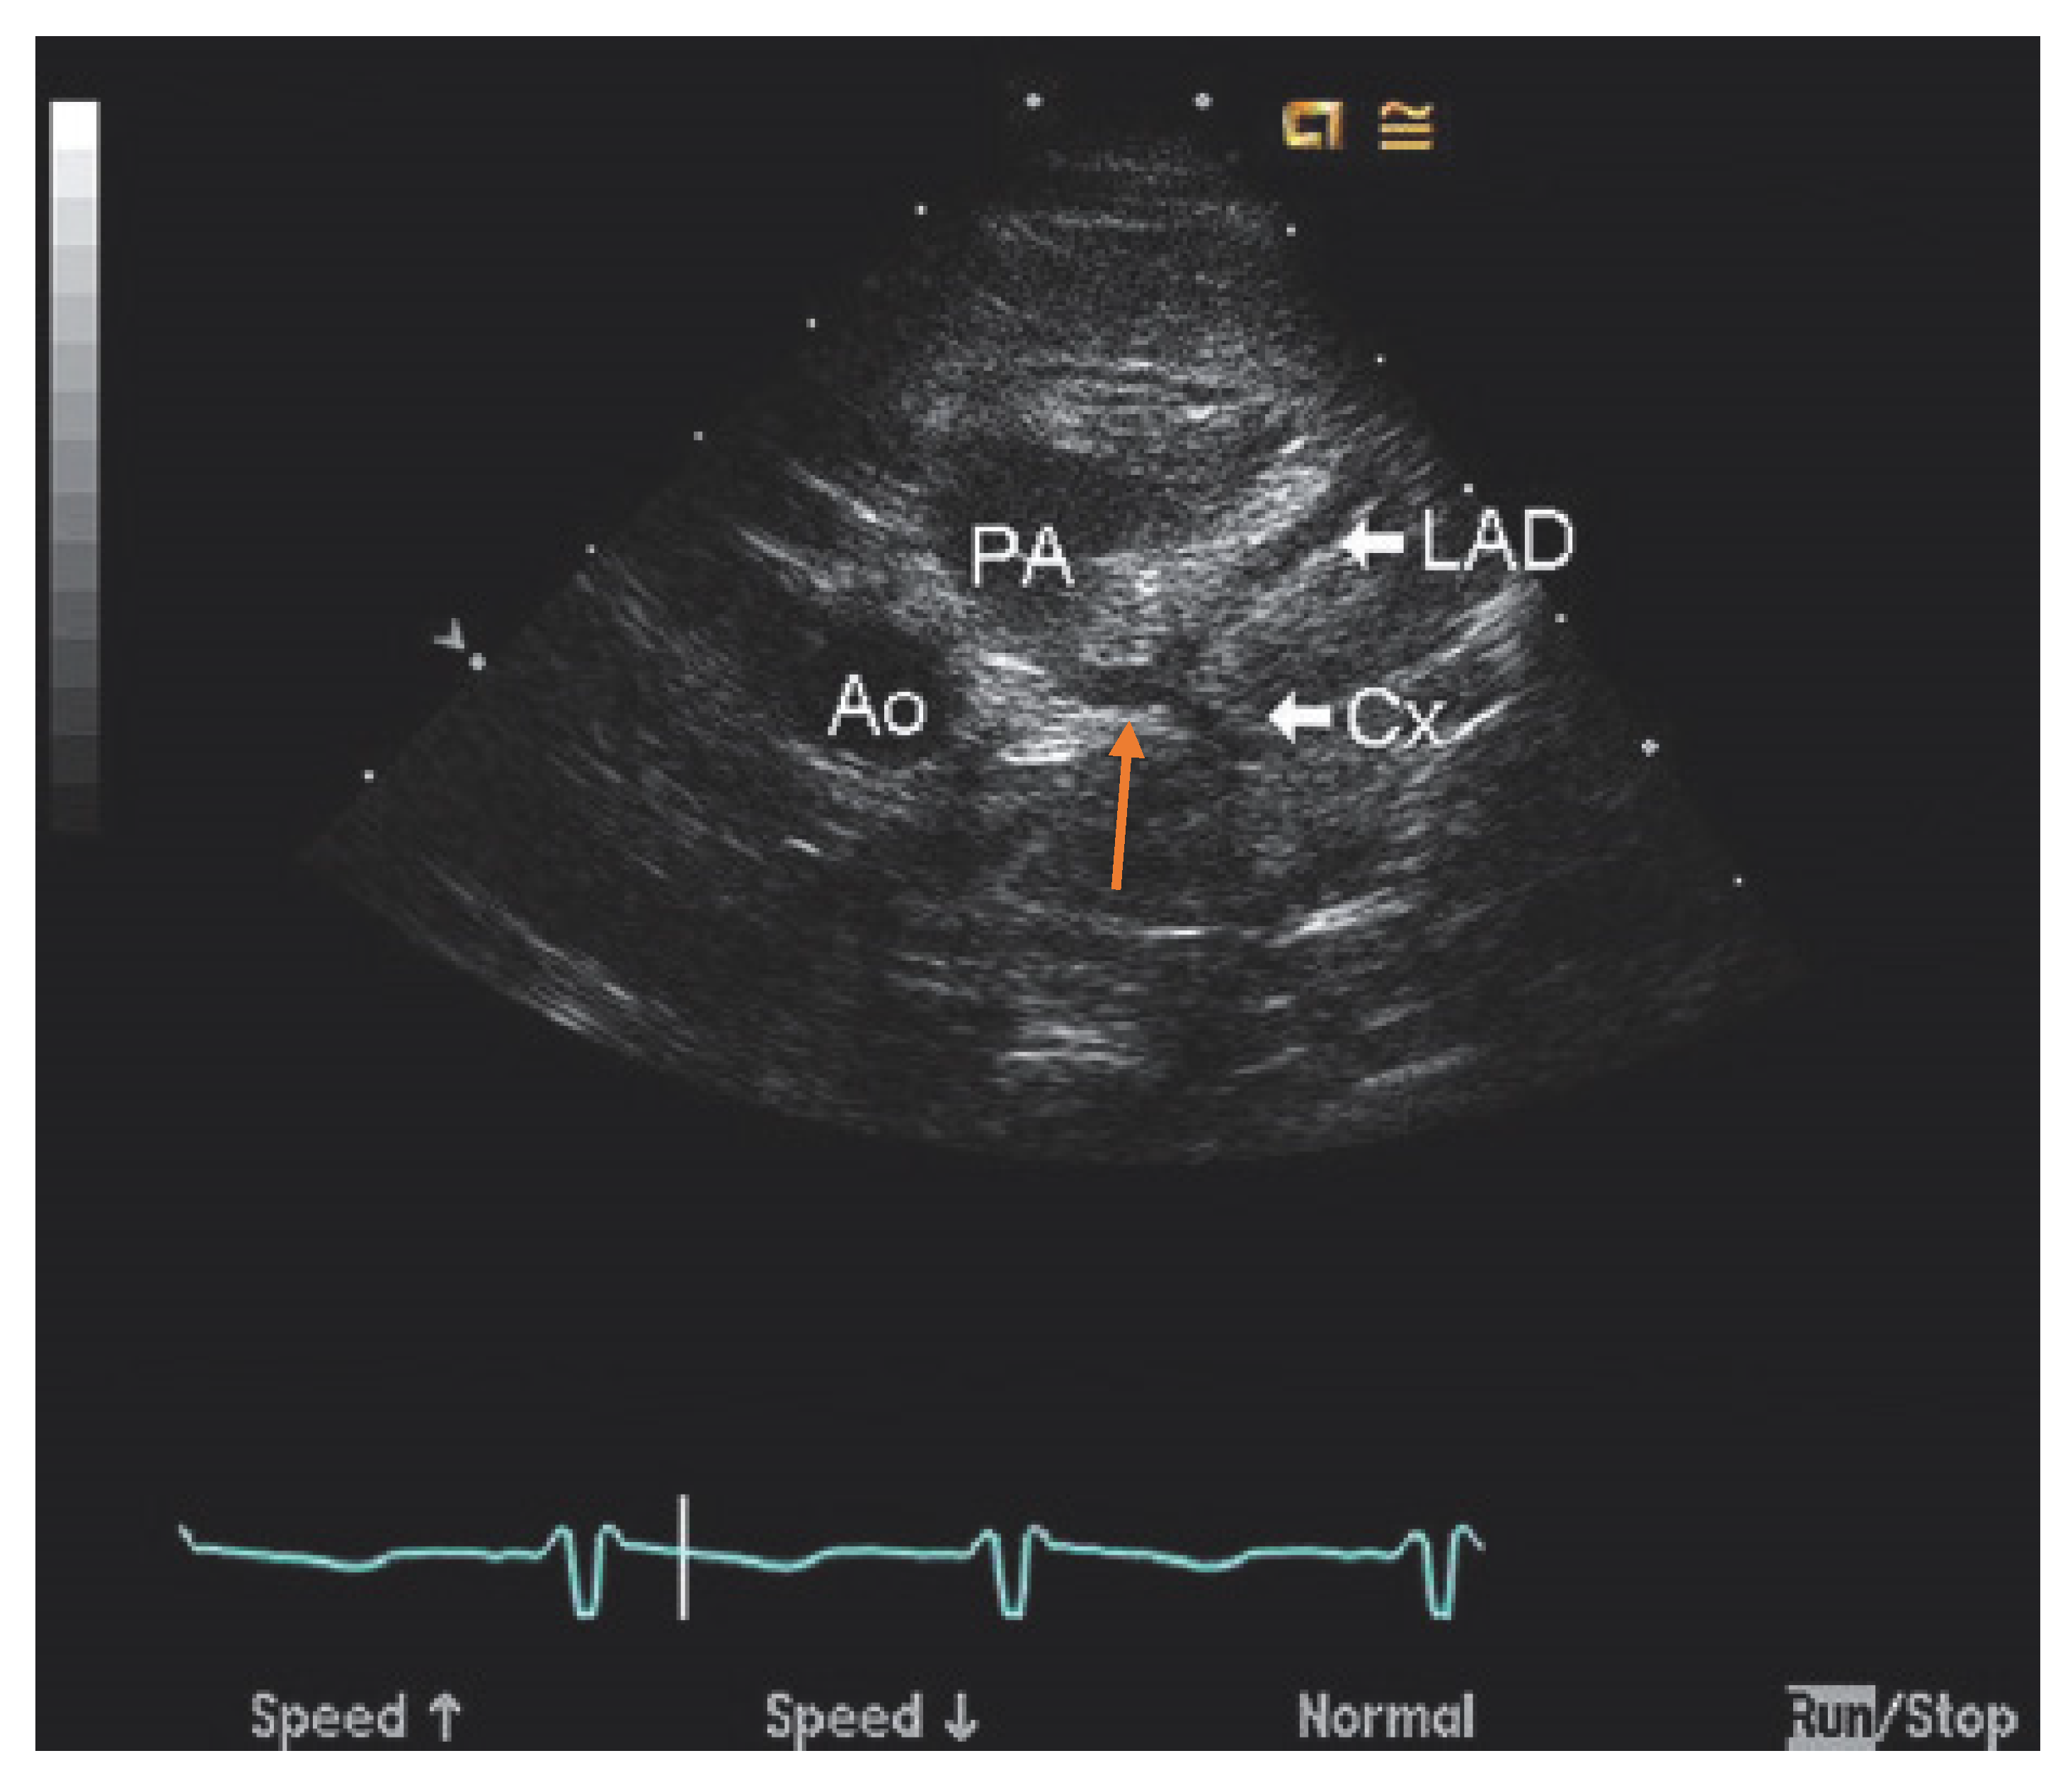

Invasive coronary angiography (ICA) was the standard for ALCAPA diagnosis as it depicted the course of the anomalous coronary artery; however, it has been largely replaced by noninvasive diagnostic testing. However, during the course of a workup for angina, the patient may undergo ICA and be found to have ALCAPA incidentally. Typical findings on ICA include a dilated and tortuous right coronary artery with multiple collaterals to the left coronary system; anomalous flow into the pulmonary artery can also be seen (Figure 1) [7]. Transthoracic echocardiogram (TTE) with color Doppler is a safe, readily available, inexpensive, and portable noninvasive method for initial investigation used in all patients (Table 1). Echocardiographic findings indicative of ALCAPA include visualization of the left coronary artery originating from the pulmonary artery (Figure 2), retrograde flow from the left coronary artery to the pulmonary artery (Figure 3), dilated and tortuous right coronary artery, lack of the left coronary artery at aortic origin, significant and dilated collateral coronary arteries, mitral regurgitation, left ventricular dysfunction with regional wall motion abnormalities, and enhanced echogenicity of papillary muscles [9,10,11]. The parasternal short-axis acoustic window on TTE provides the best views of the origins of the coronary arteries. Increased flow in the minor coronary arteries due to the collateral flow from the right to the left coronary artery may be detected by lowering the Nyquist limit. In younger patients with dilated right coronary artery, collateral arterial flow in the ventricular septum may be seen and misdiagnosed as multiple trabecular ventricular septal defects. In order to distinguish between these two, pulse-wave Doppler should be performed: continuous flow in the collateral vessels is noted in patients with ALCAPA, while systolic flow into the right ventricle is noted in patients with ventricular septal defects [11]. Transthoracic echocardiogram, while fast and easy, has poor spatial resolution, making it difficult to identify and visualize the arteries; thus, it should be supplemented with further diagnostic testing such as computed tomography angiography (CTA), magnetic resonance angiography (MRA), or ICA [4].

Figure 2. Echocardiography of anomalous left coronary artery from the pulmonary artery (ALCAPA) obtained from the parasternal short axis view at the base of the heart reveals anomalous origin of the left coronary artery (orange arrow) from the posterior aspect of the pulmonary artery (PA) far from the aorta (Ao). It divides into the left anterior descending artery (LAD) and left circumflex artery (Cx). Used with permission from Eidem, B. W.; Cetta, F.; O’Leary, P. W. Echocardiography in Pediatric and Adult Congenital Heart Disease, 3rd ed.; Wolters Kluwer: Alphen am Rhein, The Netherlands, 2021; pp. 514–530. [13].